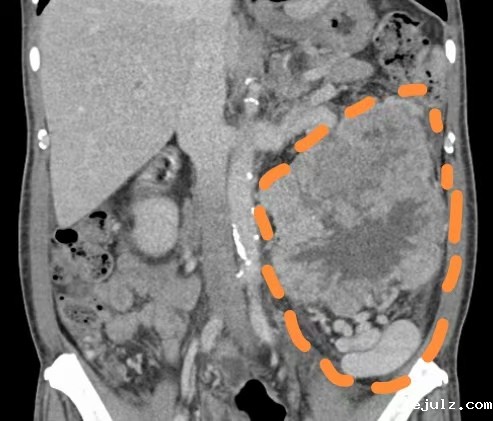

71岁的杨伯(化名)一年前在香港体检时,发现左肾占位性病变,但当时未及时处理。2025年4月复查时,左肾肿瘤体积已增长至20cm左右。而且伴随明显体重下降、头晕等症状,高度怀疑有肾恶性肿瘤的可能。

“由于患者肿瘤占据大部分左侧腹腔、盆腔,手术空间相对较小,传统开放手术创伤大、出血多、恢复慢,而患者高龄且身体状况复杂,对手术耐受性要求极高。”港大深圳医院泌尿外科程小宝副顾问医生介绍。

患者左肾肿瘤增大至约20cm,占据了腹腔、盆腔大部分空间